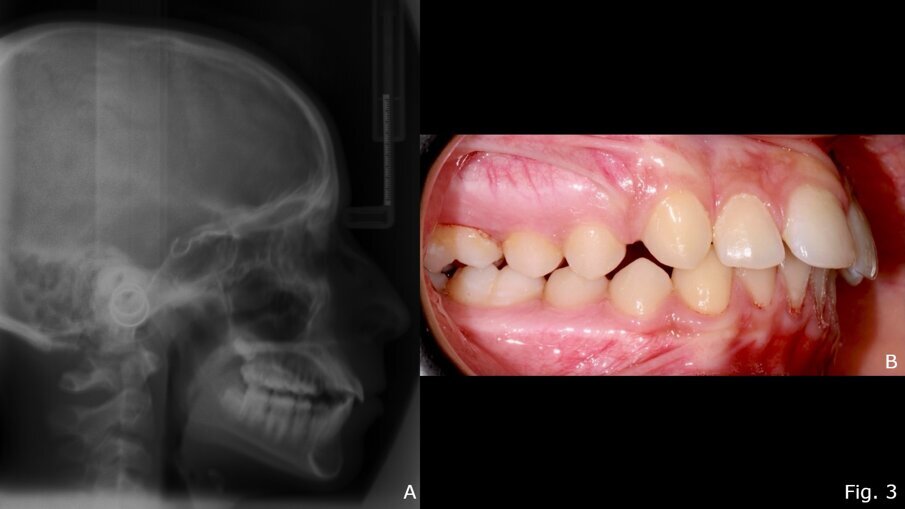

Il TB è uno dei dispositivi più comunemente usati per ottenere la correzione funzionale della malocclusione scheletrica di classe II18, 19. Provoca una riduzione statisticamente significativa dell'angolo ANB, riducendo l’OVJ e migliorando l’indice di Wits15. Il dispositivo, infatti, promuove il rimodellamento del condilo nella posizione avanzata inducendo un significativo aumento della lunghezza della mandibola (Co-Gn in mm)15, 18. Il rimodellamento adattivo può verificarsi su entrambe le superfici dell'articolazione temporo-mandibolare per migliorare la posizione della mandibola in relazione al mascellare superiore17. Un altro vantaggio è il controllo della dimensione verticale. Infatti, con il trattamento TB, lo sviluppo verticale si ottiene scartando gradualmente i blocchi in resina della placca, favorendo l'estrusione dei denti posteriori e livellando il piano occlusale20-22. Sul piano trasversale, l’utilizzo del TB ha effetti prevalentemente dentali rispetto a quelli scheletrici13. Uno degli svantaggi principali dell'apparecchio TB è che la correzione dell'overjet è data anche da cambiamenti dentoalveolari (60%) come la proclinazione degli incisivi inferiori23. Vari autori hanno proposto modifiche all'apparecchio TB per aggirare questo effetto indesiderato24-26. Ad esempio, l'uso contestuale dell'ancoraggio con mini-viti può fornire un controllo assoluto sulla posizione degli incisivi inferiori, aumentando così la correzione ortopedica nella terapia miofunzionale di classe II27. TB sembra essere particolarmente efficace nei casi di II classe in cui prevale la componente di ipoplasia mandibolare15, 28 (Figg. 2, 3).

Fig. 3 - Teleradiografia latero-laterale post-trattamento con Twin-Block (A); Foto occlusale destra post-trattamento (B).

Alcuni studi dimostrano che la correzione del retrognatismo mandibolare con un apparecchio TB in pazienti in crescita non solo migliora il profilo facciale e la relazione intermascellare, ma aumenta anche le dimensioni delle vie aeree superiori37, 38, 39, riducendo così il rischio di futuri problemi respiratori40. Per questo è considerato un dispositivo adatto al trattamento dei bambini affetti da sindrome da apnea-ipopnea del sonno (SAHS)40-44 (Fig. 3).